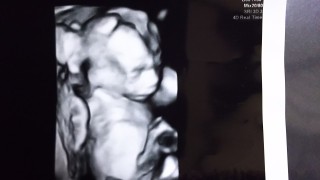

身長は14.5㎝で順調でした☆ BPDは39.4㎜で18w相当だと言われました! 今回は初めてお顔が見えました♪ 思ってたよりも顔立ちがハッキリしててビックリ! 狭そうな表情をしながら、腕を伸ばしたり足を伸ばしたりしてましたw 私は細身のためか、16w5dで初胎動を感じました♪それから毎日ポコポコ動いてて、ちょっとずつ活発に暴れてる感じがします(*^^*) 次の健診では性別が分かるといいな~